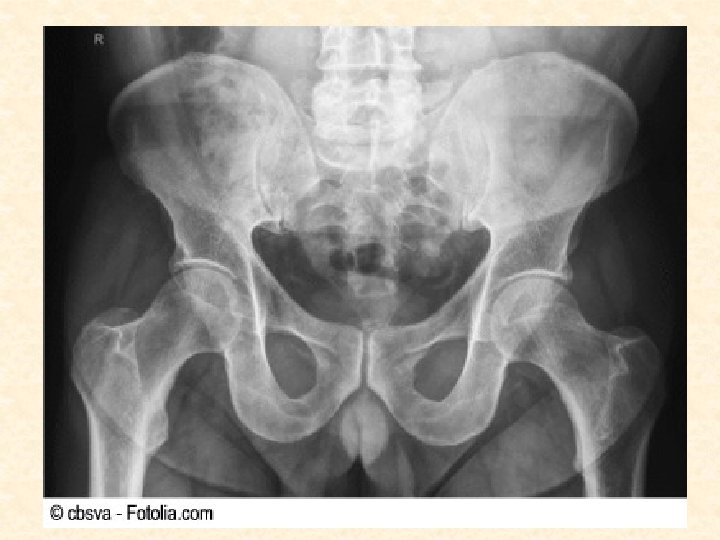

TÉCNICAS DE IMAGEN DEL CUERPO VIVO a. Radiología convencional: - Se utiliza una energía (radiación) que interaccione con el objeto y posteriormente se recoge en un receptor adecuado (placa radiográfica). - Por este procedimiento se obtiene una representación bidimensional de un objeto tridimensional en la que se superponen todas las estructuras atravesadas por la radiación.